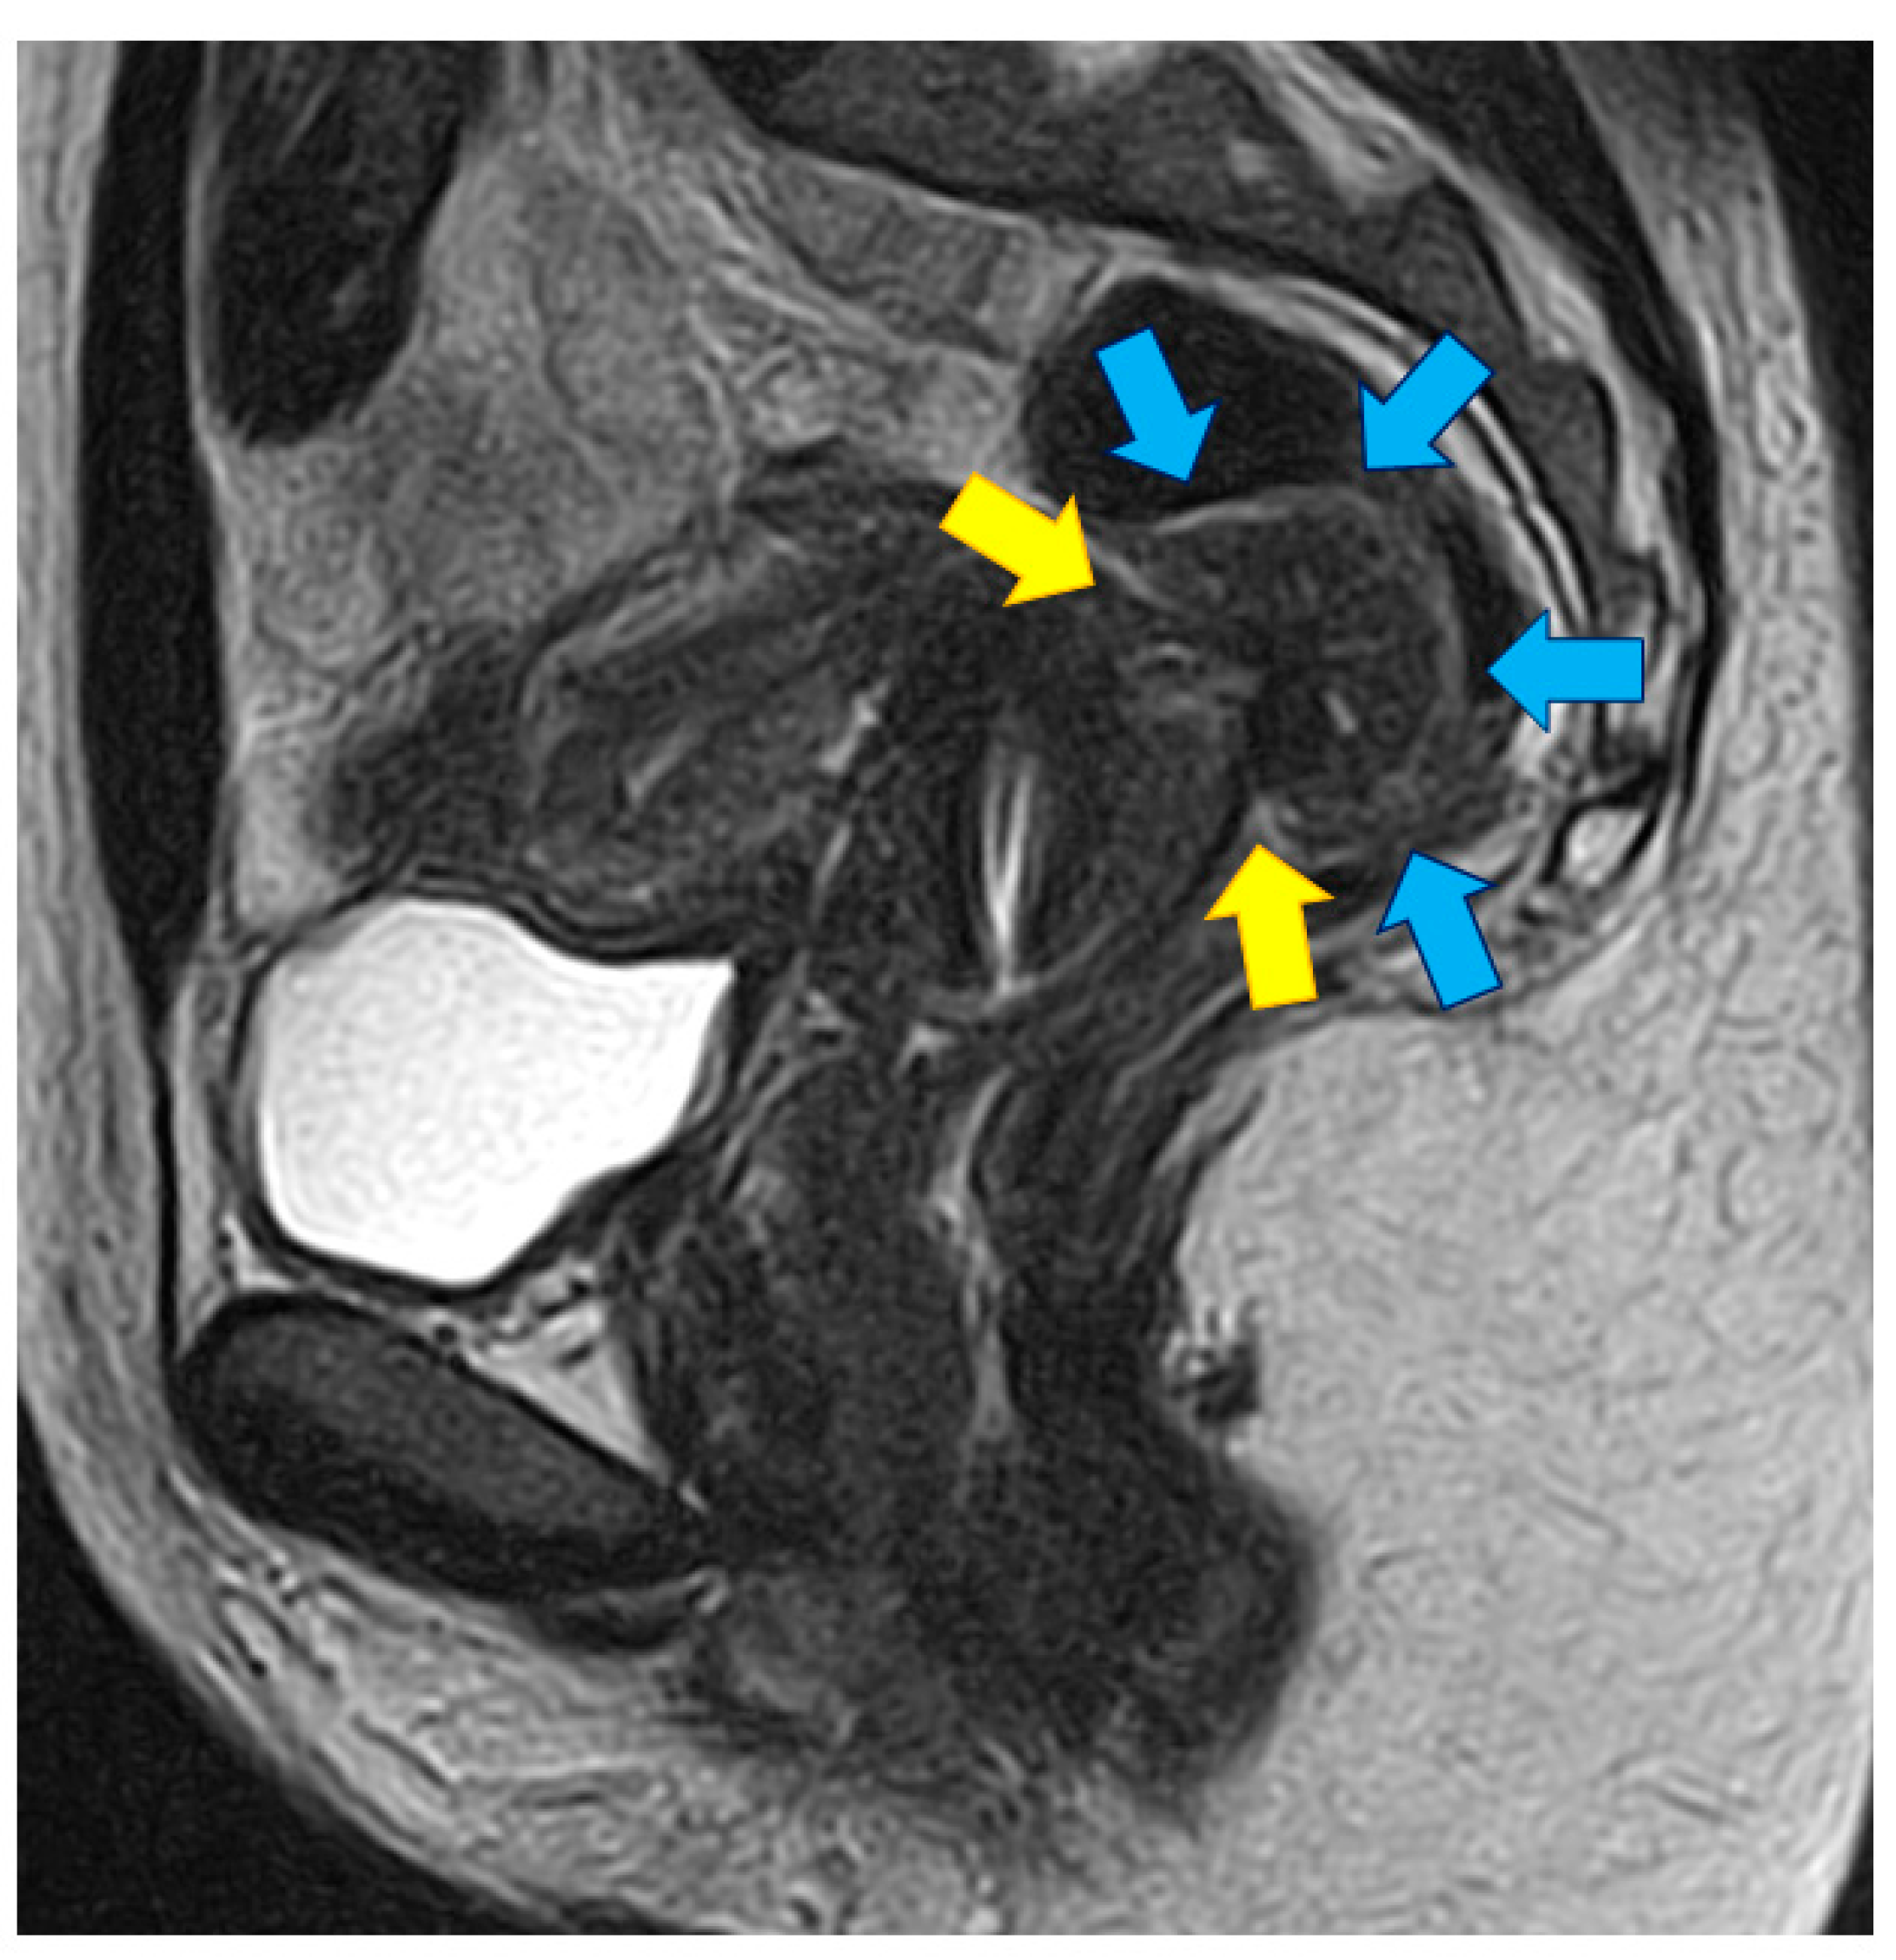

- Bazot, M.; Bharwani, N.; Huchon, C.; Kinkel, K.; Cunha, T.M.; Guerra, A.; Manganaro, L.; Buñesch, L.; Kido, A.; Togashi, K.; et al. European society of urogenital radiology (ESUR) guidelines: MR imaging of pelvic endometriosis. Eur. Radiol. 2017, 27, 2765–2775. [Google Scholar] [CrossRef]

- Bazot, M.; Kermarrec, E.; Bendifallah, S.; Daraï, E. MRI of intestinal endometriosis. Best Pract. Res. Clin. Obstet. Gynaecol. 2021, 71, 51–63. [Google Scholar] [CrossRef] [PubMed]

- Chapron, C.; Tosti, C.; Marcellin, L.; Bourdon, M.; Lafay-Pillet, M.C.; Millischer, A.E.; Streuli, I.; Borghese, B.; Petraglia, F.; Santulli, P. Relationship between the magnetic resonance imaging appearance of adenomyosis and endometriosis phenotypes. Hum. Reprod. 2017, 32, 1393–1401. [Google Scholar] [CrossRef]

- Donnez, J.; Dolmans, M.M.; Fellah, L. What if deep endometriotic nodules and uterine adenomyosis were actually two forms of the same disease? Fertil. Steril. 2019, 111, 454–456. [Google Scholar] [CrossRef]